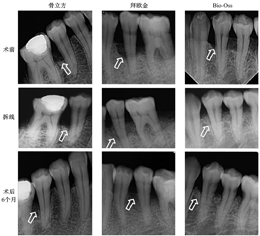

术后6个月,3组的临床和影像学指标较术前均得到明显的改善(均P<0.05)(表2、图2)。在组间比较中,3组的PD降低(ΔPD)、CAL改善(ΔCAL)、RBH改善(ΔRBH)的差异均无统计学意义(均P>0.05),如图3所示。术后6个月,影像学检查结果表明,3个组别中均可见原骨缺损区有新骨形成,且骨密度与周围骨组织近似(图4)。

骨立方是我国自主研发的含Ⅰ型胶原与羟基磷灰石的人工合成骨,具有良好的生物相容性、安全性及骨再生效果。本研究中,骨立方联合GTR获得(2.3 ± 1.64)mm的临床附着增加(ΔCAL)。虽然,骨立方组术后拆线时根尖片检查显影欠佳,但随着新骨形成,显影问题逐渐得到改善(图4)。

同种异体骨最大的优势是含有骨形成蛋白成分,能促进间充质干细胞迁移、黏附和成骨向分化。与自体骨相比,异体骨因缺少活细胞,而具有较强的骨传导作用,且解决了自体骨取材有限、第二伤口等限制[12],但其骨诱导作用较弱。同种异体骨通过酒精脱脂、盐酸脱矿、冻干辐照等方法制备而成。拜欧金即是以此方法制备的一类脱钙冻干骨。有研究结果表明,Bio-Oss和脱钙冻干骨的新骨形成量接近,但略低于自体骨[13]。本研究中使用拜欧金联合GTR获得了(2.90± 1.14)mm的临床附着增加(ΔCAL),该结果与使用脱钙冻干骨植入牙周骨下袋缺损的研究结果近似[(2.61 ± 0.68)mm][14]。